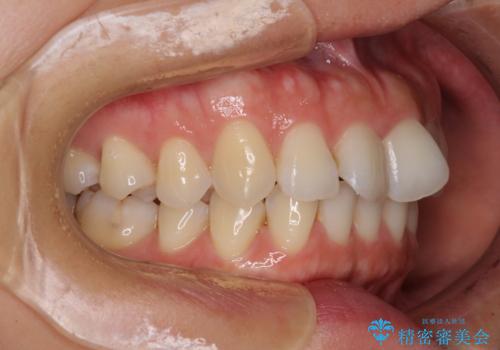

- 捻れた前歯が飛び出しており、口が閉じにくいとのことで来院された患者様です。

出っ歯というわけではないものの、前歯の捻転により口唇が押し出されている状態でした。

親知らずを抜去し、歯列全体を後方に移動させつつ、IPR(歯と歯の間を削る)でスペースを獲得し、インビザラインを用いて叢生を解消しながら前歯の突出を改善することとしました。

骨格的に上下正中がずれていたため、奥歯がしっかりと噛み合うか心配でしたが、ずれているなりに、しっかりとした咬み合わせとなりました。